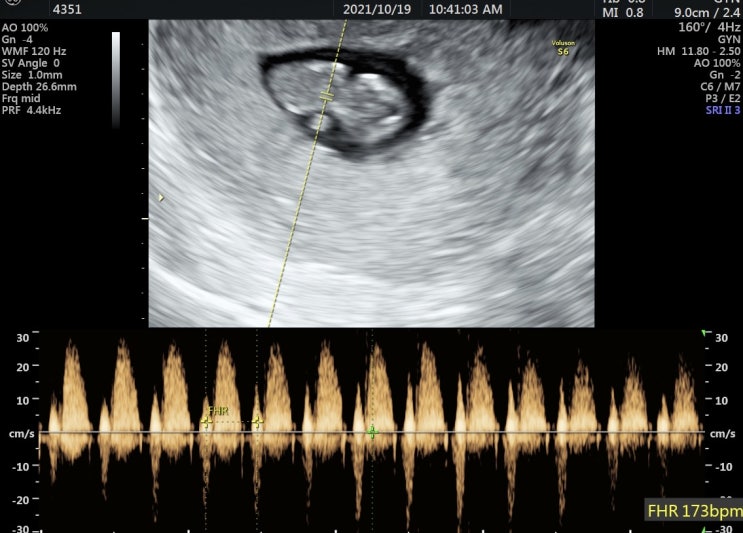

[찰떡일기??] 임신10-12주(임신초기): 청첩장모임/1차기형아검사/인천서울여성병원

10월 26일 5-8주에 했던 입덧과는 차원이 다른 9-12주 입덧 남들한테 힘든 얘기 하는 거 정말 안 좋아해서 ...

[찰떡일기??] 임신 12주: 인천서울여성병원에서 1차기형아검사한 후기(니프티검사/인터그레이티드검사/통합검사)

??걱정인형인 나에게 임신은 걱정의 연속 ➰임신 4주: 자궁외임신 걱정 ➰임신 7주: 고사난자 걱정 ...